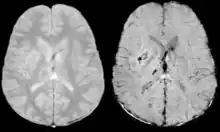

Images of CAA collected at 1.5 T. Left, conventional T2* (TE=20 ms), center, SWI processed magnitude image (TE=40 ms) and right, SWI phase image (TE=40 ms)

Gradient recalled echo (GRE) imaging is the conventional way to detect hemorrhage in CAA, however SWI is a much more sensitive technique that can reveal many micro-hemorrhages that are missed on GRE images.[7] A conventional gradient echo T2*-weighted image (left, TE=20 ms) shows some low-signal foci associated with CAA. On the other hand, an SWI image (center, with a resolution of 0.5 mm x 0.5 mm x 2.0 mm, projected over 8mm) shows many more associated low-signal foci. Phase images were used to enhance the effect of the local hemosiderin build-up. An example phase image (right) with yet higher resolution of 0.25 mm x 0.25 mm x 2.0 mm shows a clear ability to localize multiple CAA-associated foci.